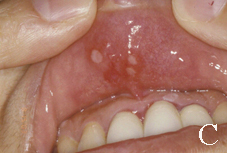

在台灣的發生率約10.5%,臨床上復發性口腔潰瘍有三種型態,小型、大型、泡疹型(如:圖一)。小型的復發性口腔潰瘍為1公分以下,潰瘍約7至14天會復原,小型的復發性口腔潰瘍雖然很小,但有時相當的疼痛。大型的復發性口腔潰瘍直徑約1-3公分,通常要2-6個星期才會癒合,且可能會結痂,大型的復發性口腔潰瘍好發於唇黏膜、軟?等處。泡疹型復發性口腔潰瘍,數目很多,集結成團,且常復發,每個潰瘍直徑約1-3 mm,有時多個小潰瘍會集結起來成為大潰瘍,泡疹型復發性口腔潰瘍約7-10天會痊癒,通常從成人期開始發生,且好發於女性患者。

圖一: 復發性口腔潰瘍。(A)發生於舌尖黏膜之小型復發性口腔潰瘍病變。(B)發生於右下唇黏膜之大型復發性口腔潰瘍病變。(C)發生於上唇黏膜之泡疹型復發性口腔潰瘍病變。